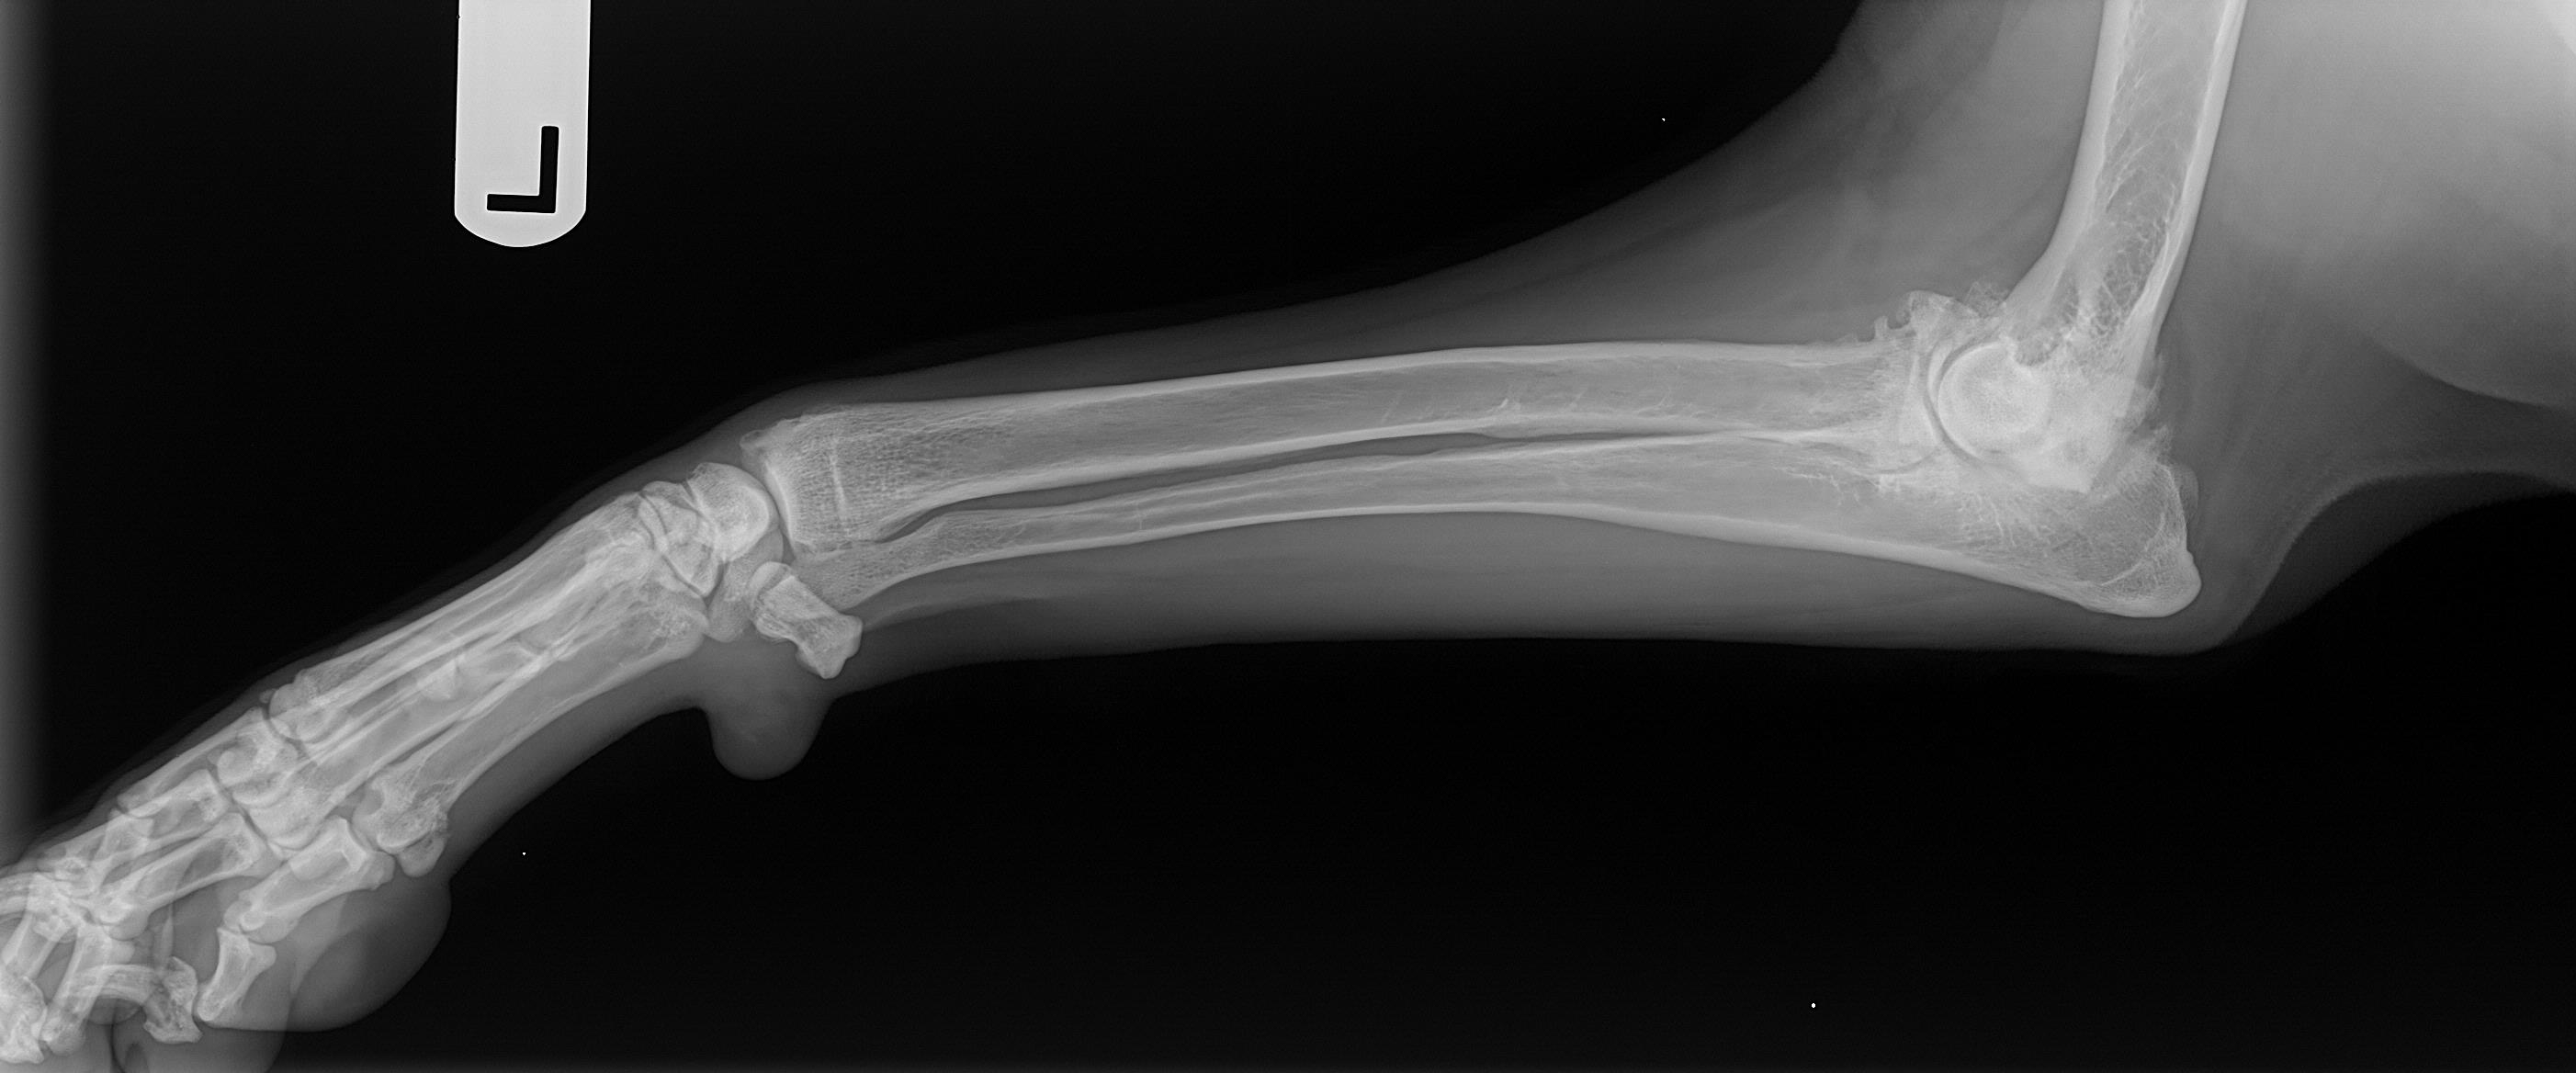

List 99+ Pictures Leg Pictures Of Dog Arthritis Superb Dog Paws Arthritis Dog arthritis is a chronic, inflammatory condition affecting your pet’s joints, causing discomfort and stiffness. Arthritis can’t be cured but fortunately, there are several treatment options to slow it’s progression and manage pain. Dog arthritis is a condition that affects the joints of dogs. Learn how to spot the signs of arthritis in dogs, treatment options and ways to manage. Dog Paws Arthritis.